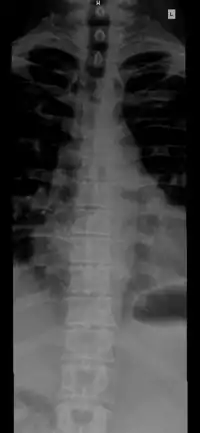

![]() The human vertebral column and its regions | |

The vertebral column, also known as the backbone or spine, is the core part of the axial skeleton in vertebrate animals. The vertebral column is the defining characteristic of vertebrate endoskeleton in which the notochord (a flexible collagen-wrapped glycoprotein rod) found in all chordates has been replaced by a segmented series of mineralized irregular bones (or sometimes, cartilages) called vertebrae, separated by fibrocartilaginous intervertebral discs (the center of which is a notochord remnant).[1] The dorsal portion of the vertebral column houses the spinal canal, a cavity formed by alignment of the neural arches that encloses and protects the spinal cord.

The number of vertebrae in a region can vary but overall the number remains the same. In a human vertebral column, there are normally 33 vertebrae.[3] The upper 24 pre-sacral vertebrae are articulating and separated from each other by intervertebral discs, and the lower nine are fused in adults, five in the sacrum and four in the coccyx, or tailbone. The articulating vertebrae are named according to their region of the spine. There are 7 cervical vertebrae, 12 thoracic vertebrae and 5 lumbar vertebrae. The number of those in the cervical region, however, is only rarely changed,[4] while that in the coccygeal region varies most.[5] Excluding rare deviations, the total number of vertebrae ranges from 32 to 35.[6] In about 10% of people, both the total number of pre-sacral vertebrae and the number of vertebrae in individual parts of the spine can vary.[7][8][9] The most frequent deviations are: 11 (rarely 13) thoracic vertebrae, 4 or 6 lumbar vertebrae, 3 or 5 coccygeal vertebrae (rarely up to 7).[9]

The vertebrae in the human vertebral column is divided into different regions, which correspond to the curves of the vertebral column. The articulating vertebrae are named according to their region of the spine. Vertebrae in these regions are essentially alike, with minor variation. These regions are called the cervical spine, thoracic spine, lumbar spine, sacrum, and coccyx. There are seven cervical vertebrae, twelve thoracic vertebrae, and five lumbar vertebrae.

Individual vertebrae are named according to their region and position. From top to bottom, the vertebrae are:

- Cervical spine: 7 vertebrae (C1–C7)

- Thoracic spine: 12 vertebrae (T1–T12)

- Lumbar spine: 5 vertebrae (L1–L5)

- Sacrum: 5 (fused) vertebrae (S1–S5)

- Coccyx: 4 (3–5) (fused) vertebrae (Tailbone)